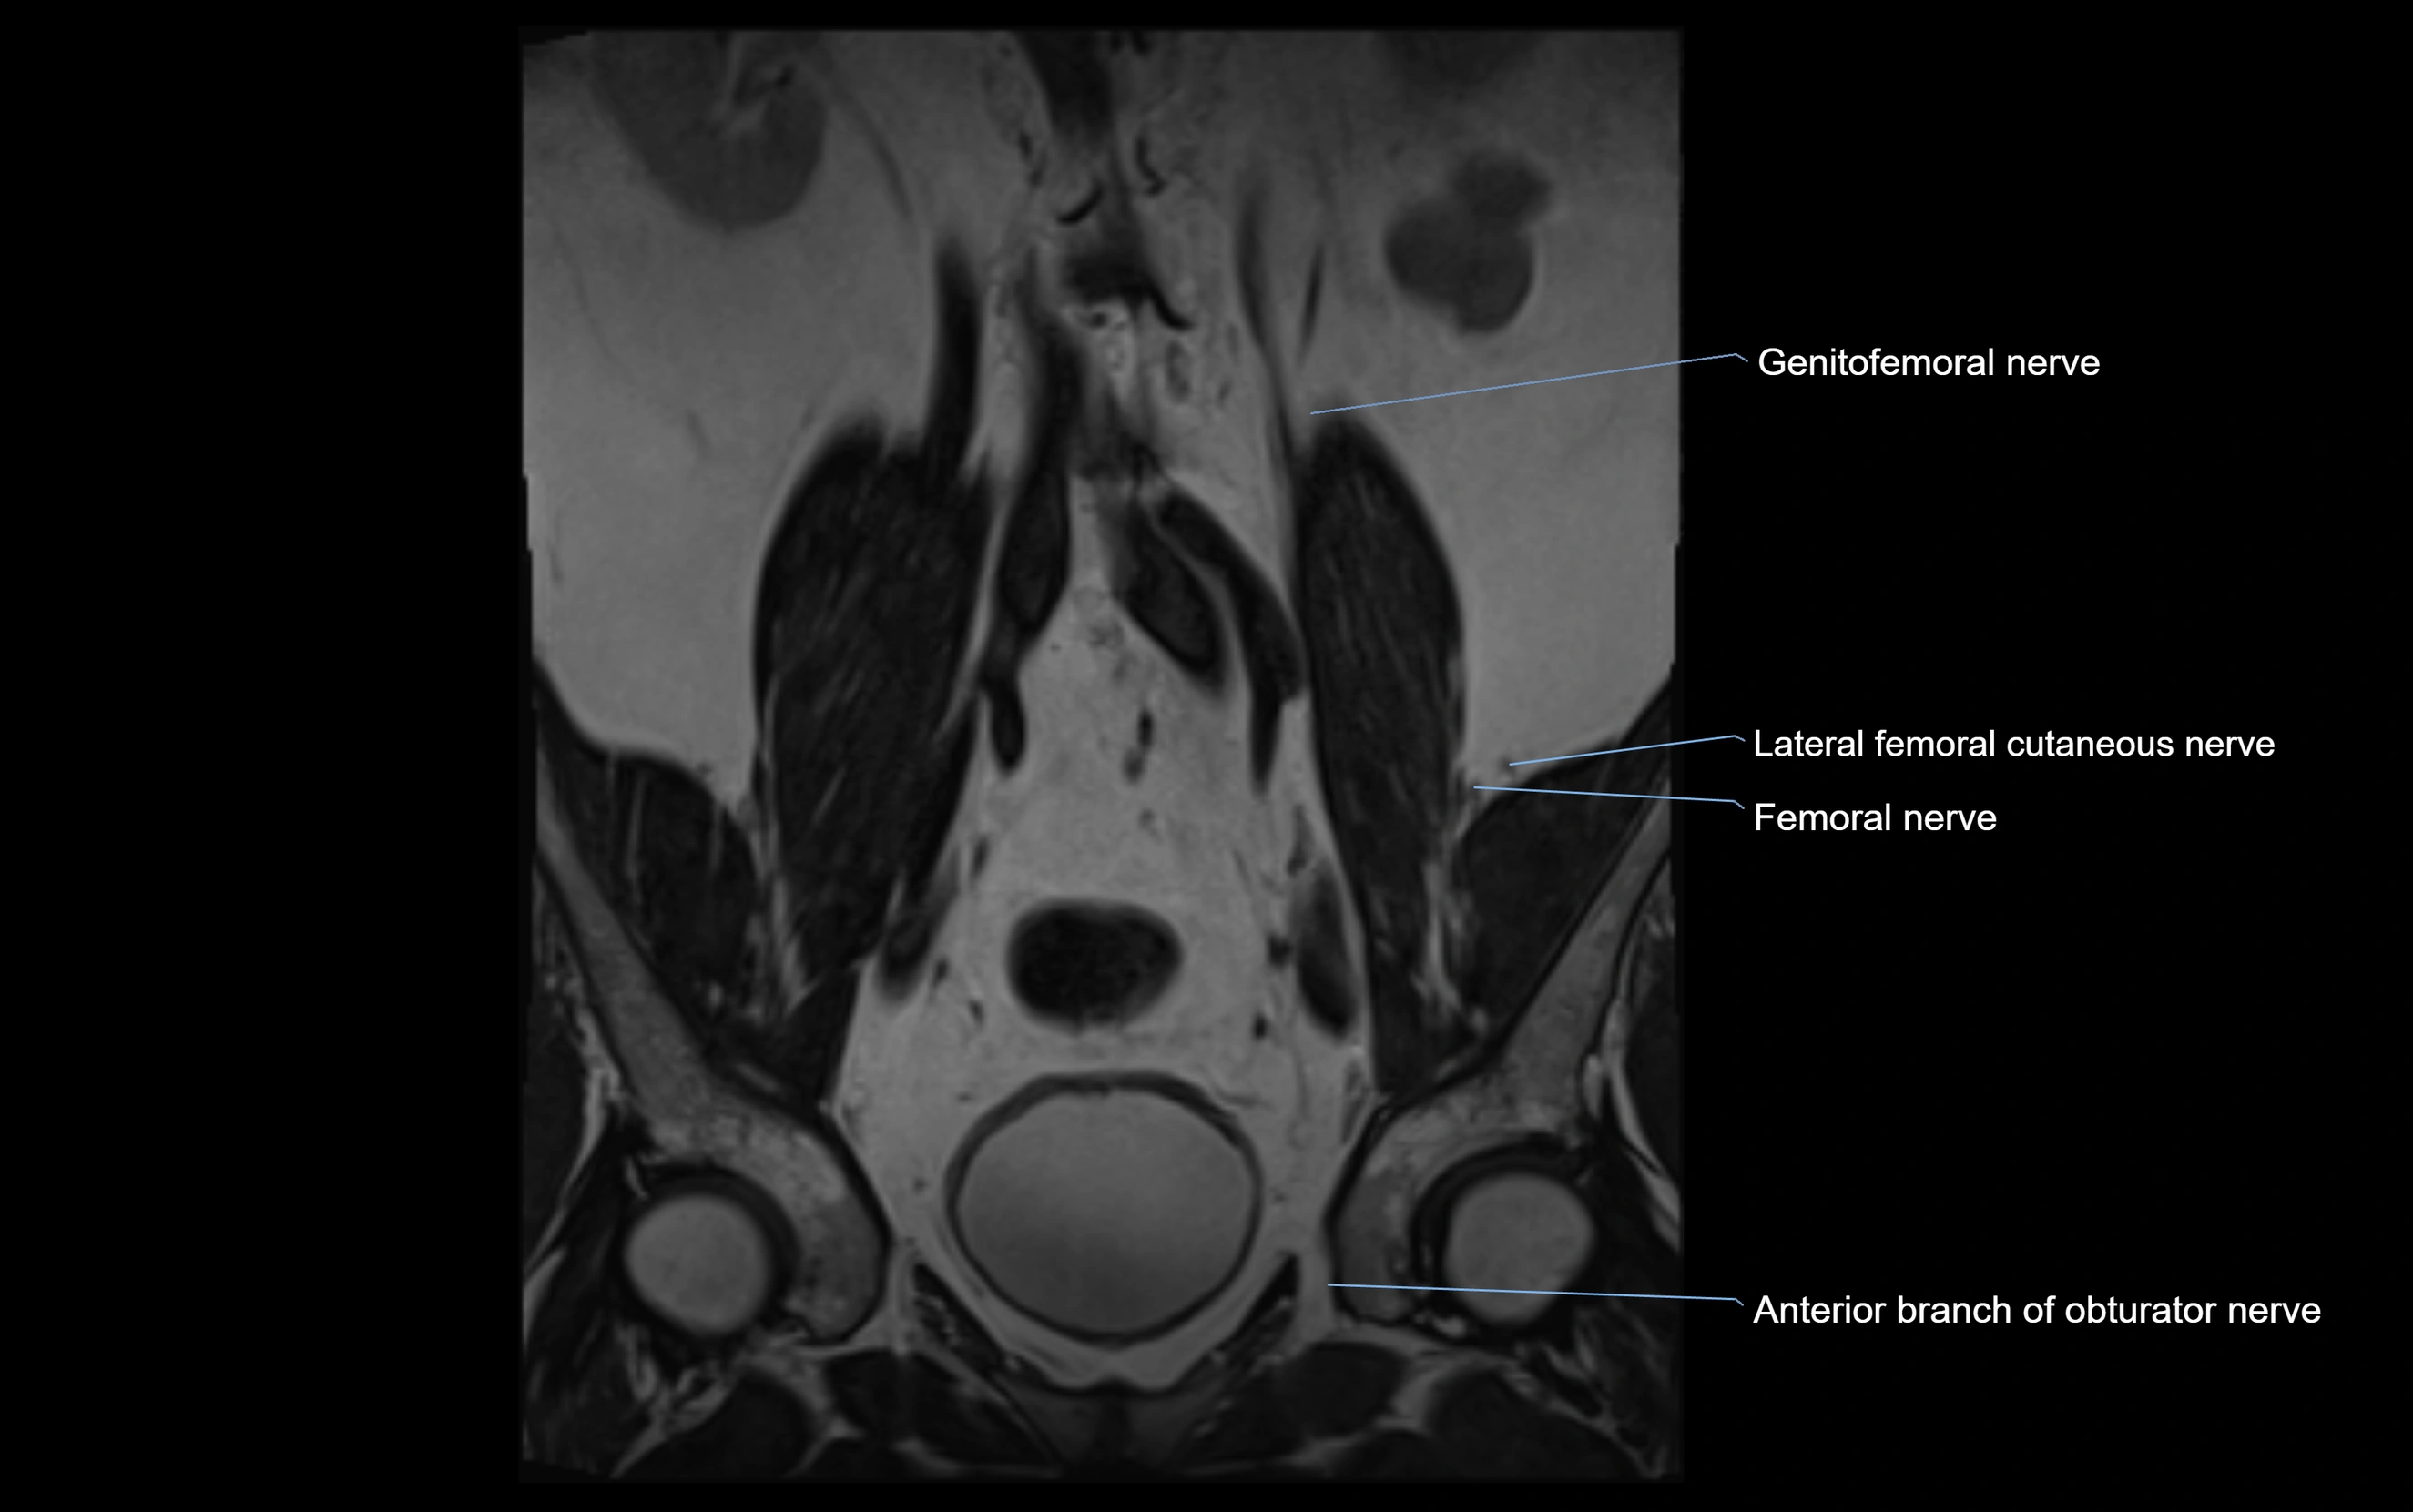

MRI Appearance

T1-weighted images:

• Nerve appears as a very thin low-to-intermediate signal intensity structure

• Surrounded by bright fat, aiding visualization

T2-weighted images:

• Nerve shows intermediate to mildly hyperintense signal compared to muscle

• Pathological involvement appears brighter

STIR (Short Tau Inversion Recovery):

• Normal nerve appears dark

• Inflamed or entrapped nerve appears bright hyperintense

T1 Fat-Sat Post-Contrast:

• Normal nerve enhances minimally

• Pathologic nerve (neuritis, entrapment, tumor infiltration) shows focal or diffuse enhancement

3D T2 SPACE / CISS:

• Nerve appears intermediate to mildly hyperintense compared to muscle

• Surrounded by bright fat or CSF, improving visualization

• Best sequence for mapping small pelvic nerves such as the anococcygeal